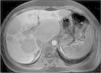

En la ecografía y en la resonancia magnética (RM) abdominal practicadas, se apreció una hepatomegalia con múltiples lesiones sólidas (20–30) que afectaban de forma difusa a ambos lóbulos hepáticos, sin que el parénquima preservado presentara signos de patología (fig. 1).